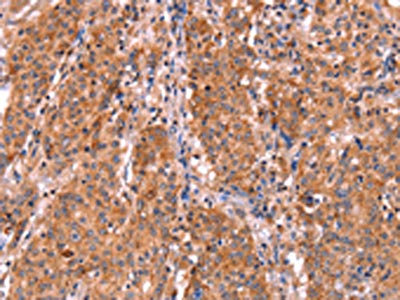

The image on the left is immunohistochemistry of paraffin-embedded Human gastic cancer tissue using CSB-PA196653(ABI1 Antibody) at dilution 1/40, on the right is treated with synthetic peptide. (Original magnification: ×200)